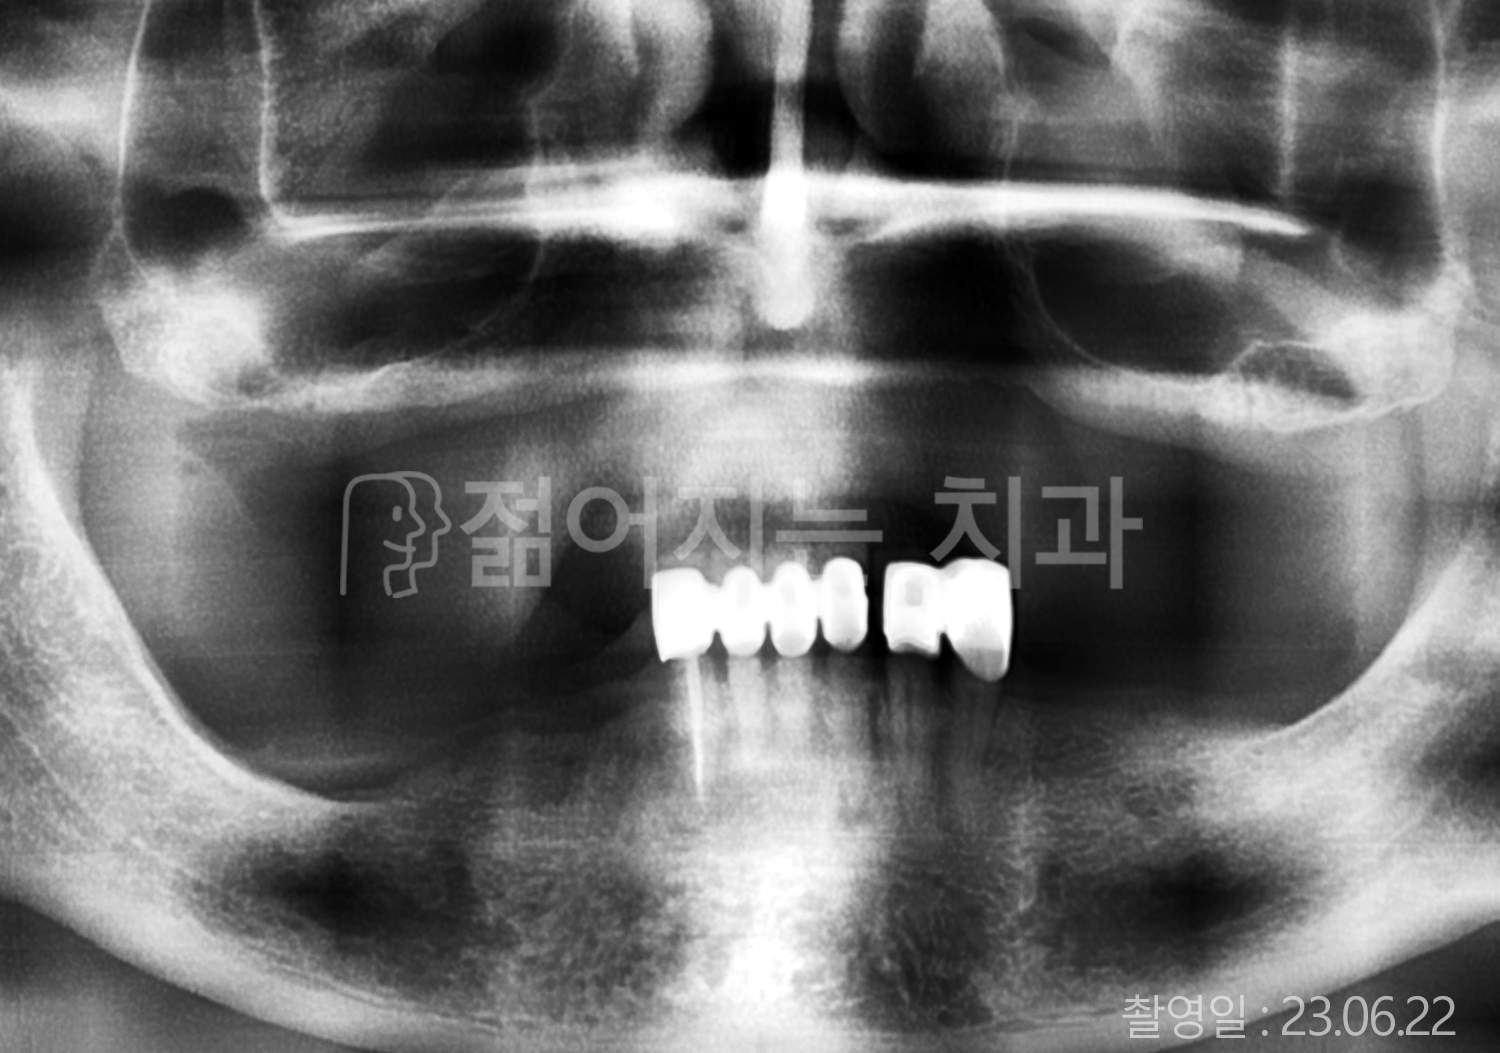

• 60대 고혈압, 고지혈증 전체치아 10개 이상 임플란트

• 70대 전체치아 10개 이상 임플란트

• 60대 전체치아 10개 이상 임플란트

• 50대 전체치아 10개 이상 임플란트

• 50대 고혈압, 고지혈증 전체치아 10개 이상 임플란트

• 60대 고혈압, 당뇨, 고지혈증 전체치아 10개 이상 임플란트

• 80대 고혈압, 당뇨, 골다공증 전체치아 10개 이상 임플란트

• 60대 고혈압 전체치아 10개 이상 임플란트

• 60대 고지혈증 전체치아 10개 이상 임플란트

• 60대 당뇨 전체치아 10개 이상 임플란트